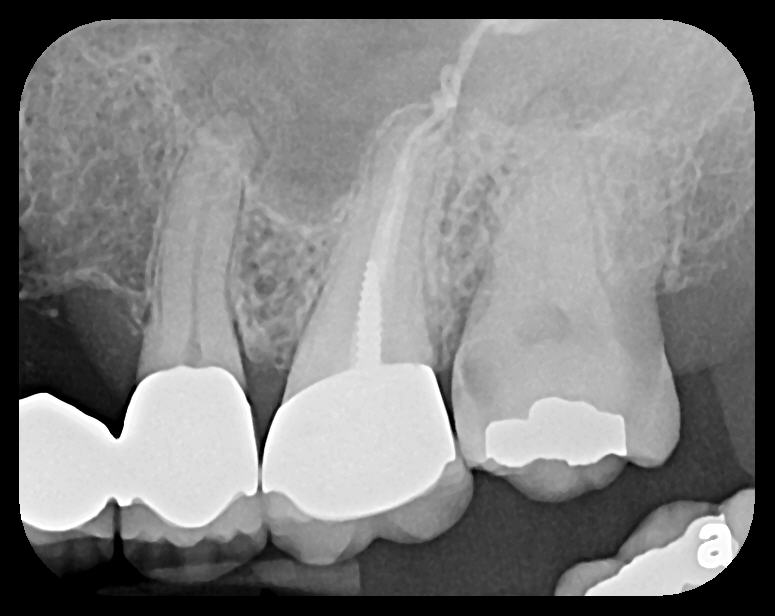

Fig 9. Endodontic obturation overfill visible on PA radiograph, which is

escaping the apex of tooth No. 14 and extruding into the left maxillary

sinus. A pathologic sinus congestion, in the form of a slight radiopacity

within the sinus, is noted in response to the foreign material.

Figure 9